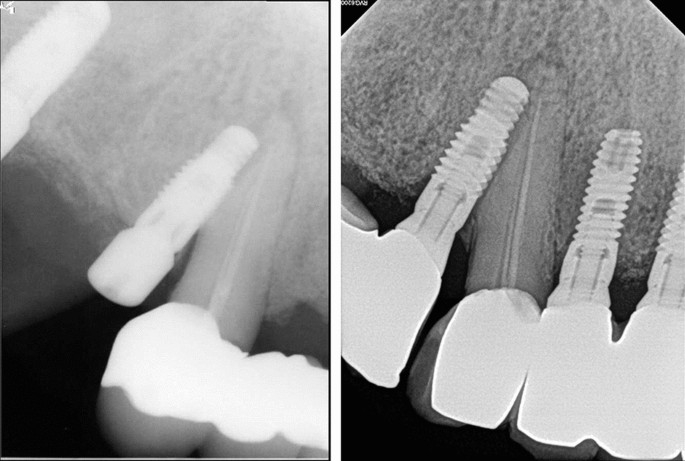

Among the natural teeth that were injured, five of 32 teeth had already undergone root canal treatment (RCT) prior to implant placement. Five of these non-vital teeth functioned well without unusual changes, regardless of the extent of invasion (Fig. 1, Table 3). Of the 27 non-treated teeth, seven had a new RCT after implant injury due to the presentation of clinical symptoms and/or signs. Three of the seven new RCT teeth were subsequently extracted after 39 months, 7 years, and 14 years of function, respectively. One of the seven new RCT teeth was intentionally replanted after endodontic treatment and external root resorption was observed later. Although apical radiolucency was found before surgery, one of the 27 teeth was maintained without symptoms. Subsequently, 19 of 27 teeth (70.4%) remained vital and had no abnormal response during follow-up.

The periapical views of groups I, II and III are shown in Figs. 2, 3, 4. Of the 32 teeth, ten were in group I, ten in group II, and 12 in group III (Table 3). In group I, two out of five new endodontically treated teeth were extracted with symptoms. Consequently, five of 10 teeth in group I had events. The remaining five teeth consisted of two endodontically treated teeth prior to implant surgery and three vital teeth with non-specific findings. Fig. 2 shows the healing aspect of one of three vital teeth in group I and a replaced implant with a new one due to failure in osseointegration, which was the only case of implant failure in the study. In group II, one of the vital teeth had symptoms and underwent RCT. In group III, a new RCT was performed on one vital tooth, which was subsequently extracted. There were no implant failures in groups II and III. Events among the three groups showed significant differences (Chi-square test, p=0.008).

Direct invasion of the root (Group I); (left above) January 2013. (Right above) Osseointegration failed and a new implant was replaced. Arrows indicate trace of the old implant outline, February 2013; (left below) May 2013; (right below) injured tooth remained vital during 7-year functions, September 2020.

Normal function of the injured teeth indicated healing after trauma from the implant. In Fig. 2, a trace of the implant form in the damaged root is seen even after replacement with the new implant. The trace remained for 7 years, and the radiolucent outline of the implant shape was associated with periodontal ligament regeneration. This regeneration proves the results of animal studies on the healing process of injured root surfaces with miniscrews. Hembree et al.17 showed that the periodontal ligament recovered to normal widths when miniscrew placement displaced the bone into the periodontal ligament. Kang et al.18 also reported the repair of moderately injured roots with osteoid and/or cementoid tissues with a normal periodontal ligament. The root cementum or periodontal ligament regenerated in 2-3 weeks after damage22.